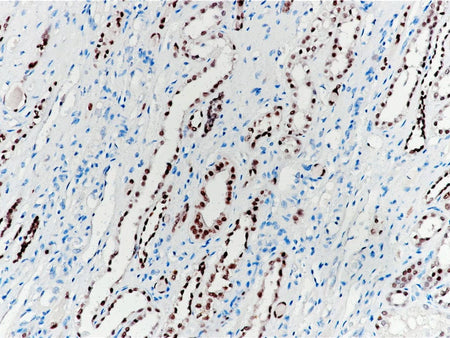

Pax-2 Monoclonal Antibody Stored at -20°C

Applications IHC-P

Cellular Localization nucleus

Tissue Specificity Kidney

Pax-2 is a member of Pax transcription factor family. Pax-8 and Pax-2 participate in the formation of renal organs. In non-tumor tissues, Pax-2 is expressed in glomerular wall epithelial cells, renal collecting duct cells, atrophic renal tubular cells, ovarian surface epithelial cells, fallopian tubes, endometrium, endometrium. In primary tumors, Pax-2 is mainly expressed in renal cell carcinoma and nephrogenic tumor. Recent studies have shown that Pax-2 can be used as an effective immunohistochemical marker for the judging of renal epithelial cell tumors and some gynecological tumors.